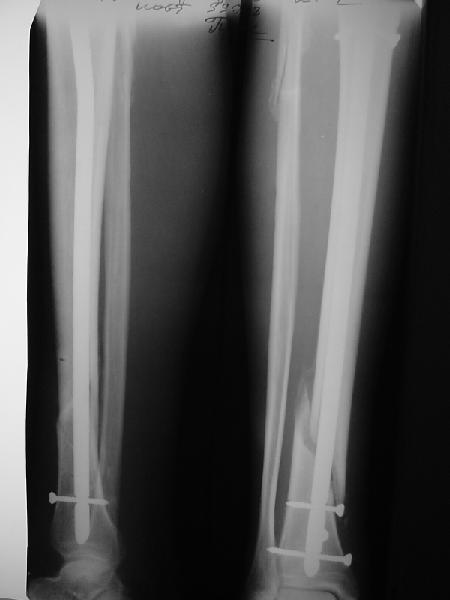

Ok. А также и следующий, в 3 месяца.

Это наглядная демонстрация возможности ранней полной нагрузки при нестабильном по оси повреждении, причем не в самых благоприятных механических условиях - при плохом сопоставлении, со слабым фиксатором.

Сверху - один статический винт, а снизу - три. Что раньше сломается? Конечно, он потом и нижние сломал, и Вы правы, если бы верхний динамичесий винт уже уперся бы в нижний край отверстия, будь гвоздь подлинее, перфорировал бы сустав как пить дать.

Как я уже говорил, мы сделали выводы из этого и других подобных случаев. Очевидно, решений проблемы два - либо уменьшить нагрузку, либо увеличить прочность фиксатора. Первое решение работает не со всеми больными, так что пошли по второму пути - мы больше не используем гвозди с запирающими винтами диаметром 4 мм.